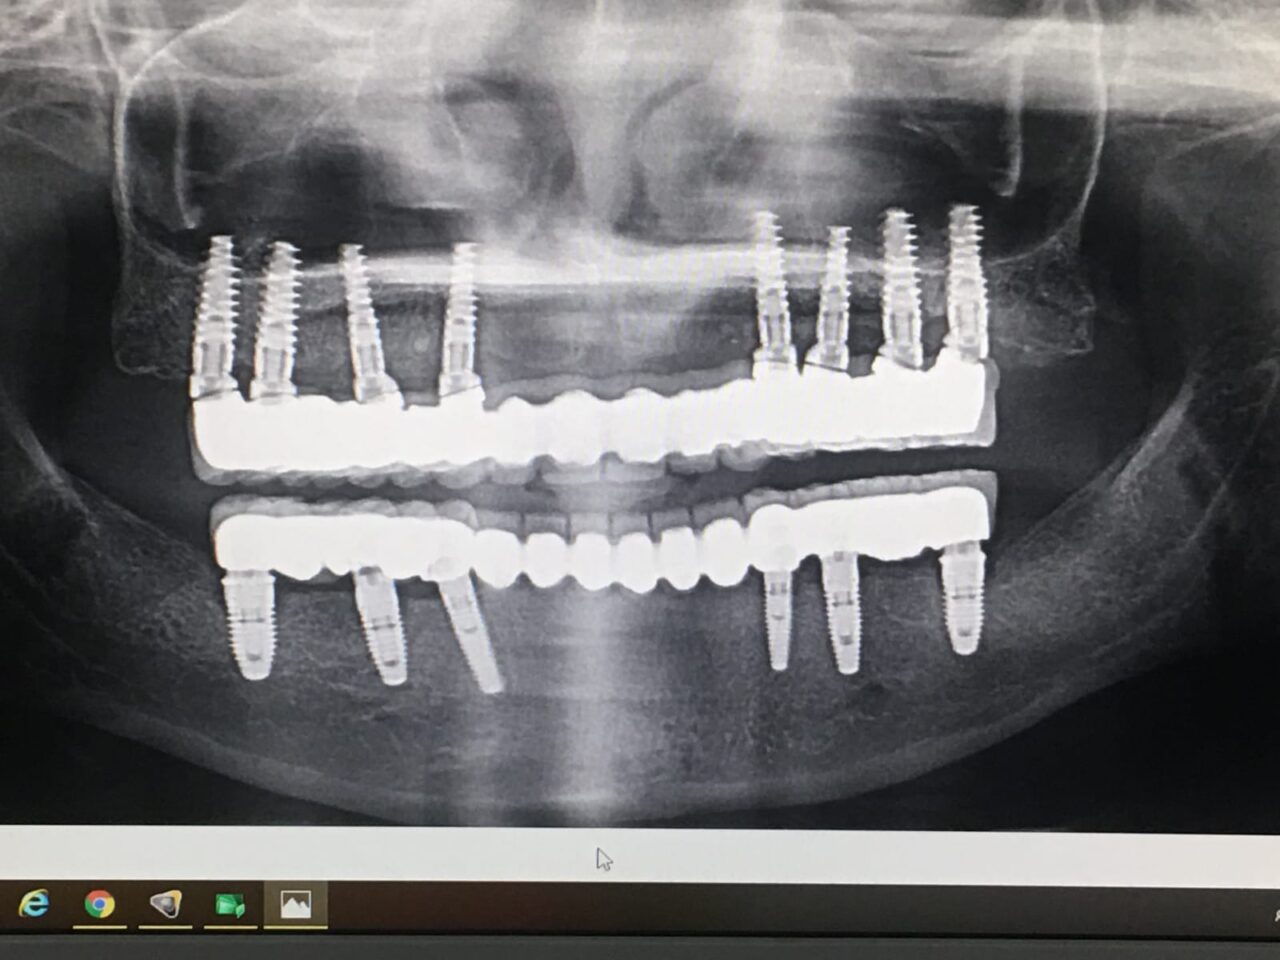

C. Full-Arch Fixed Prosthesis (Full-Arch Bridge / Hybrid Denture)

✪Entire jaw replaced with a fixed prosthesis on multiple implants (usually 4–8).

Common Designs:

All-on-4 / All-on-6 concept

Hybrid prosthesis (metal framework + acrylic/ceramic teeth)

Full zirconia or porcelain bridge